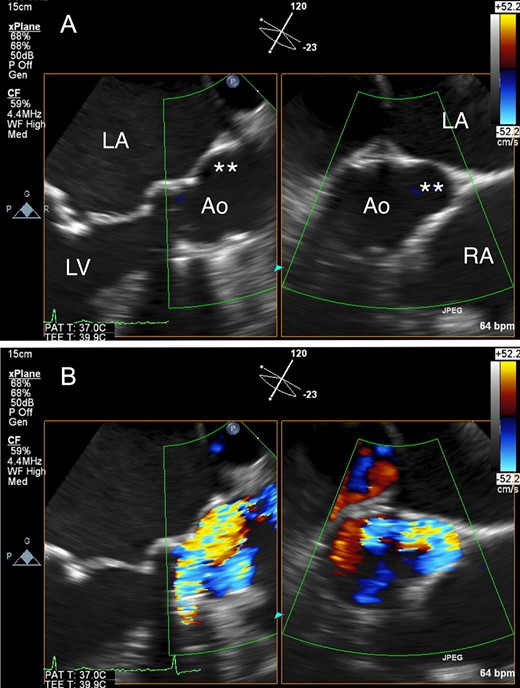

An 80-year-old woman, who had undergone aortic valve replacement with a 23-mm Björk-Shiley valve and open mitral commissurotomy at our hospital for multivalvular rheumatic heart disease at age 51, had chest tightness during exertion after many years of uneventful, asymptomatic clinical development. Follow-up transthoracic echocardiographic examinations over the past several years showed a normal left ventricular volume and ejection fraction, and moderate mitral stenosis (mitral valve area: 1.5 cm2) and an elevated peak prosthetic aortic jet velocity of 300-350 cm/s had been maintained within the boundary area without worsening. Cardiac computed tomography (CT) angiography revealed no significant obstructive coronary disease, but an unexpected saccular ascending aortic aneurysm (maximum transaortic diameter: 51 mm) arising from the posterior ascending aortic wall was observed (Fig. 1A). Transesophageal echocardiography (TEE) revealed eccentric systolic flow jets through the tilting disc valve prosthesis directly impinging on the saccular aneurysm (Fig. 2A and B, Video 1). In addition, cardiac CT angiography (systolic images) and TEE confirmed that the Björk-Shiley valve with a normal leaflet opening angle (Fig. 1C–E) was implanted with its major opening directed toward the non-coronary sinus, and was unpredictably tilted by the elevation of the prosthesis in the right-coronary sinus (Fig. 1B). The patient underwent reoperation for her ascending aortic aneurysm and possible stenosis of the prosthetic aortic valve. The ascending aorta was opened after aortic cross-clamping, and the prosthetic aortic valve and aortic aneurysm were inspected from the inside. Since the orifice of the aneurysm was located on the edge of the aortotomy suture line in the posterior wall of the ascending aorta, the lesion was probably considered a postsurgical false aneurysm. Although the Björk-Shiley valve prosthesis had no restricted leaflet motion without any obvious structural deterioration, thrombus, or abnormal pannus, it was causing an elevated transprosthetic velocity. Therefore, we decided to replace this old mechanical prosthesis with a 21-mm bovine pericardial bioprosthesis (Carpentier-Edwards Magna Ease Aortic Valve: Edwards Lifesciences, Irvine, CA, USA). The ascending aorta was replaced with a 26-mm Dacron prosthetic graft (J-Graft: Japan Lifeline Co., Ltd., Tokyo, Japan). The operative course was uneventful, and the patient recovered from surgery and has been free of complaints for almost three years.

(A) Transesophageal echocardiography (TEE) revealed a saccular ascending aortic aneurysm arising from the posterior ascending aortic wall just above the sino-tubular junction. (B) TEE with color Doppler revealed eccentric systolic flow jets through the tilting disc valve prosthesis directly impinging on the saccular aneurysm. Ao: aorta; LA: left atrium; LV: left ventricle, RA: right atrium; Double asterisk: saccular aneurysm.